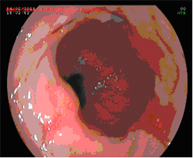

Mucosectomia endoscòpica

La mucosectomia consisteix en la resecció per via endoscòpica d'una secció de la mucosa i submucosa (en aquest cas esofàgica). Està indicada sempre que a l'endoscòpia diagnòstica s'apreciïn lesions sobreelevades a l'esòfag de Barrett.

Aquesta prova diagnòstica es realitza sense ingrés, i s'ha de realitzar una estada en observació a l'hospital de dia durant unes hores.